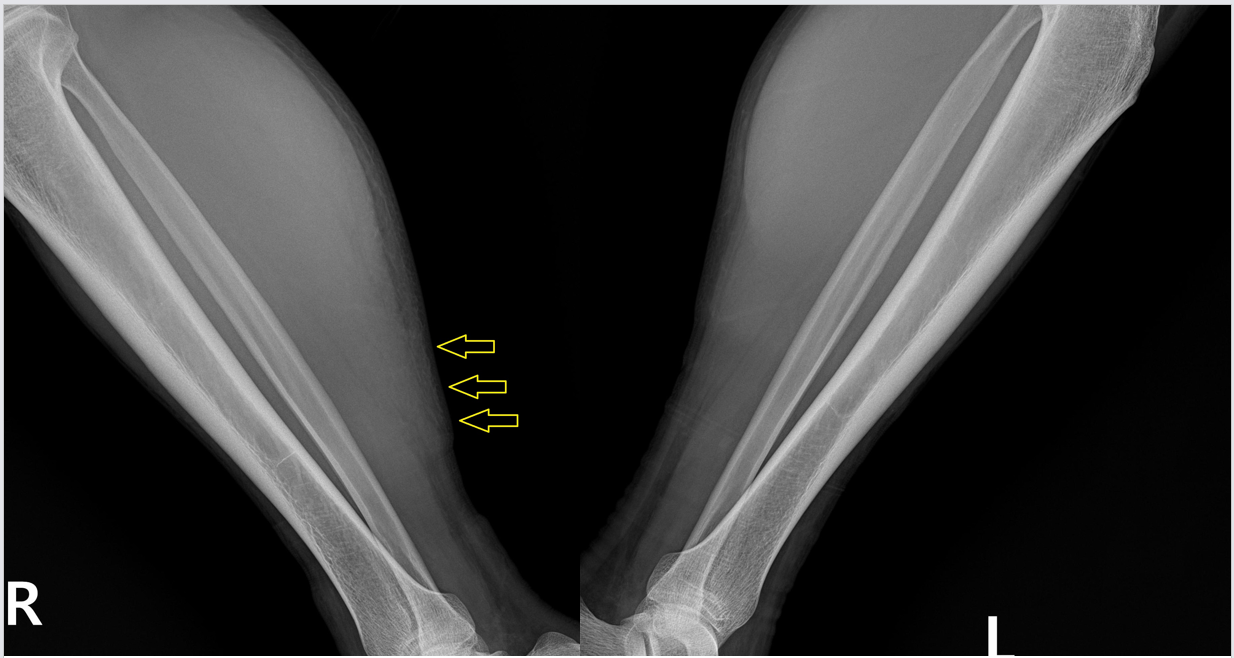

x-ray 상에서도 보면 우측 종아리 근육 부위가 좌측에 비해 더 하얗게 부어 있는걸 볼 수 있습니다. 아마도 종아리 근육이 꽤 많이 찢어진거 같습니다. 그런데 근육은 x-ray만으로는 자세히 보기가 어렵습니다. 그래서 근육을 더 정확하게 볼 수 있는 초음파 검사를 진행했습니다. 초음파 결과는....